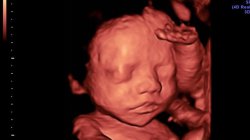

什么是四维检查?四维超声是一种超声检查。除了一般的彩色超声波功能外,它还可以对胎儿的头部和面部进行四维成像,可以清晰地显示眼睛,鼻子,嘴巴,肠道等状态,并可以帮助医...

四维彩色多普勒超声的出现可以让怀孕的母亲提前知道胎儿在腹部的样子。他们不再只是感觉到婴儿腹部的小动作,就可以看到婴儿美丽的笑容和可爱的一举一动。最重要的是要全面了...

四维超声可用于观察宫内胎儿的生长发育,清晰筛查胎儿畸形,为早期诊断胎儿先天性畸形和先天性心脏病提供准确的科学依据。那何时是进行四维超声检查的最佳时间? (1)通常,怀孕...